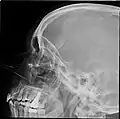

Lateral projection of the paranasal sinuses

Paranasal sinuses are a group of four paired air-filled spaces that surround the nasal cavity.[1] The maxillary sinuses are located under the eyes; the frontal sinuses are above the eyes; the ethmoidal sinuses are between the eyes and the sphenoidal sinuses are behind the eyes. The sinuses are named for the facial bones and sphenoid bone in which they are located. Their role is disputed.